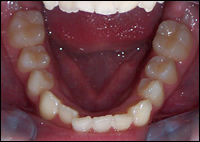

Fig 1 & 2: An 11 year old female presented with a narrow upper and lower dental arches and crowded teeth.